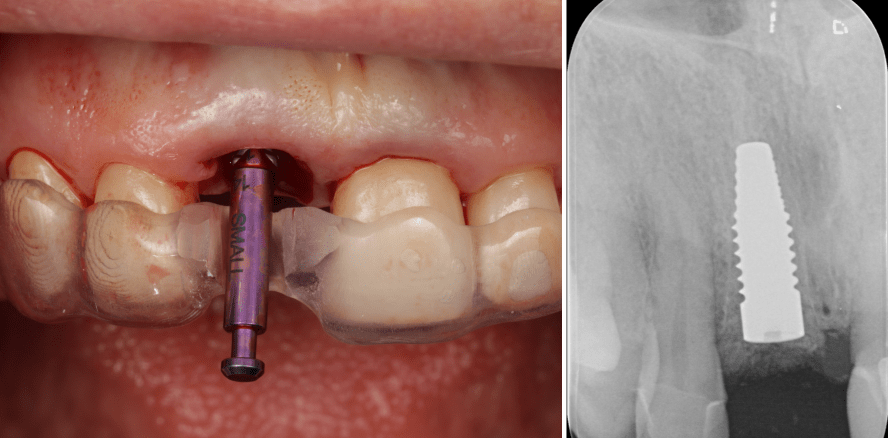

Die Extraktionsalveole wurde gesäubert und die vestibuläre Knochenwand auf ihre Kontinuität geprüft – mit dem Ergebnis, dass die Knochenwand Regio 11 keine Perforation aufwies. Nun wurde mithilfe der Orientierungsschablone eine Pilotbohrung auf 2,0 mm durchgeführt und anschließend die Richtung des noch einzubringenden Implantats mit einem Führungsstift geprüft. Unter Einhaltung des vorgegeben Bohrprotokolls wurde das Implantatbett bis zur gewünschten Größe aufbereitet, wobei auf eine Ausrichtung an der palatinalen Wand der ursprünglichen Alveole geachtet wurde. Anschließend wurde ein volllkeramisches wurzelförmiges zweiteiliges Zirkonimplantat 0,5 mm suprakrestal platziert (SICwhite tapered, 4,2/12 mm, SIC invent). Die Primärstabilität betrug 24 Ncm.

Zur prothetischen Versorgung wurde auf das Implantat der passende Scanbody aufgeschraubt und der Nachbarzahn 21 nach Entfernung der alten Krone nachpräpariert. Im Kontrollröntgenbild war zu diesem Zeitpunkt eine suffiziente krestale Knochenintegration des Implantats sichtbar. Als Schnittstelle für die okklusal verschraubbare Krone diente eine konfektionierte Klebebasis aus PEEK verbunden mit einer gefrästen und im Cut-Back-Verfahren nachgeschichteten Zirkonkrone.

Der Vertikalextraktor kann zudem auch an Grenzen stoßen. Bei gelockerten Zähnen ist er eine stets zu erwägende Option zur Entfernung ankylosierter Zähne, jedoch nicht immer erfolgreich einsetzbar. Im vorliegenden Fall machte er die Sofortimplantation einfach und vorhersagbar. Vor allem wurde ein Weichgewebstrauma von vornherein vermieden.Bei der Implantation selbst ermöglichte die Orientierungsschablone, wie geplant, eine dreidimensionale Tiefenplatzierung des Implantats circa 3 mm apikal der Schmelz-Zement-Grenze. Das verwendete Implantat weist systemimmanent eine polierte krestale Zone von 0,6 mm auf, welche eine maximal aequikrestale Platzierung des Implantats ermöglicht. Röntgenologisch ist gut erkennbar, dass der Knochen lateral in diesem Bereich leicht apikal der Implantatschulter an der Fixtur anliegt.